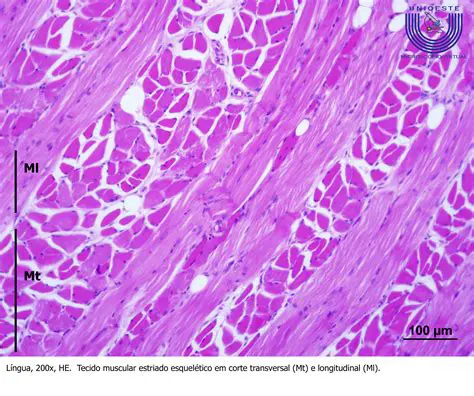

Armazenagem de calor no tecido muscular